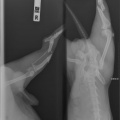

Tagumise käpa luumurd.

Koerake sattus varjupaika vigastatud käpaga. Ülevaatusel selgus, et koera käpal on mitmekordne luumurd. Pidime paigaldama ka kateetri, kuna ta ei saanud pissida (ilmselt autolöögist põhjustatud kusepõie atoonia).

Собака поступила в приют с множественным переломом ноги. Не могла пописать (видимо был удар машины и, как результат, атония мочевого пузыря). Нога в очень тяжёлом состоянии, и завтра мы кладём собаку на операционный стол.